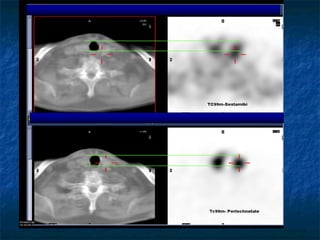

΢ύγθνηζε SPECT/CT MIBI, SPECT/CT TC99m

SPECT/CT

MIBI

1 ώνα

TC99m

(ζε άιιε μένα)

Fusion

(AMIDE)

Γπίπεδε μειέηε

δηπιήξ θάζεξ

θαη αθαίνεζεξ

πηζακά ανκεηηθή

1. Αδέκςμα παναζονεμεηδώκ

2μ αδέκςμα;

1 αδέκςμα